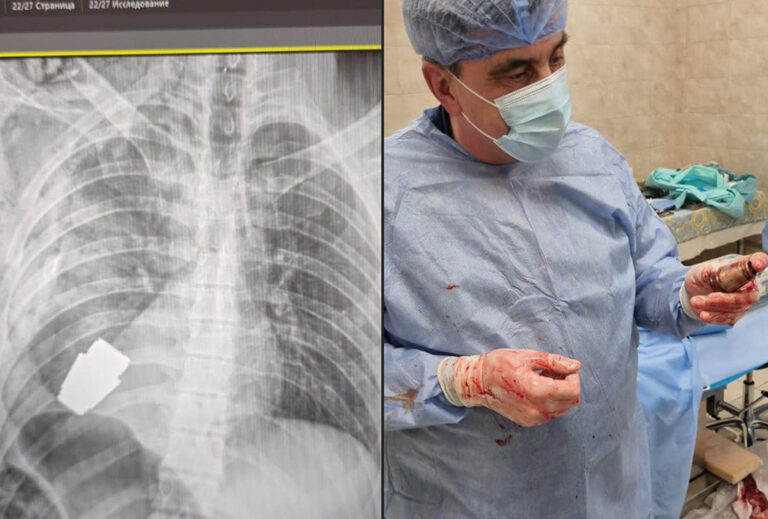

PILTUUDIS: Ukraina sõduri kehast eemaldati lõhkemata granaat

Avaldatud: 9 jaanuar, 2023Ukraina kaitseministri asetäitja Hanna Maljar jagas sotsiaalmeedias pilte sellest, kuidas Ukraina sõduri rindkerest eemaldati lõhkemata granaat.

Sõjaväearstid viisid läbi operatsiooni, et eemaldada sõjaväelase kehast lõhkemata VOG-granaat.

See eemaldati kahe sapööri juuresolekul, kes tagasid meditsiinitöötajate ohutuse.

Operatsiooni tegi Ukraina relvajõudude üks kogenumaid kirurge Andri Verba ilma elektrokoagulatsioonita, kuna granaat võis iga hetk plahvatada.

Operatiivne sekkumine õnnestus ning haavatud sõjaväelane saadeti edasisele rehabilitatsioonile ja taastumisele.